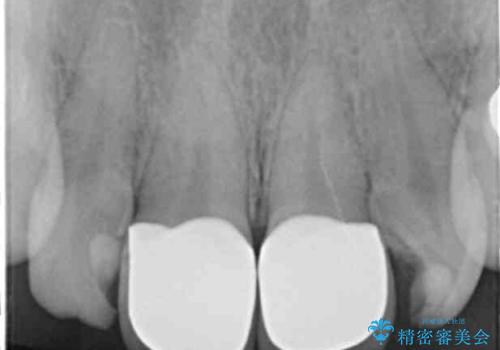

ラミネートベニヤの破折 ジルコニアクラウンによるやり替え

- 欠けてしまった前歯のラミネートベニヤと見た目の改善を求めて来院されました。

歯の大きさの不揃いと、虫歯の再発を認めたためラミネートのやりかえではなく一挙に問題の解決のできるジルコニアクラウンでの治療を計画します。